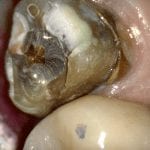

REMAINING TOOTH STRUCTURE AFTER PREVIOUS CROWN REMOVED AND THE PREPARATION REFINEMENT